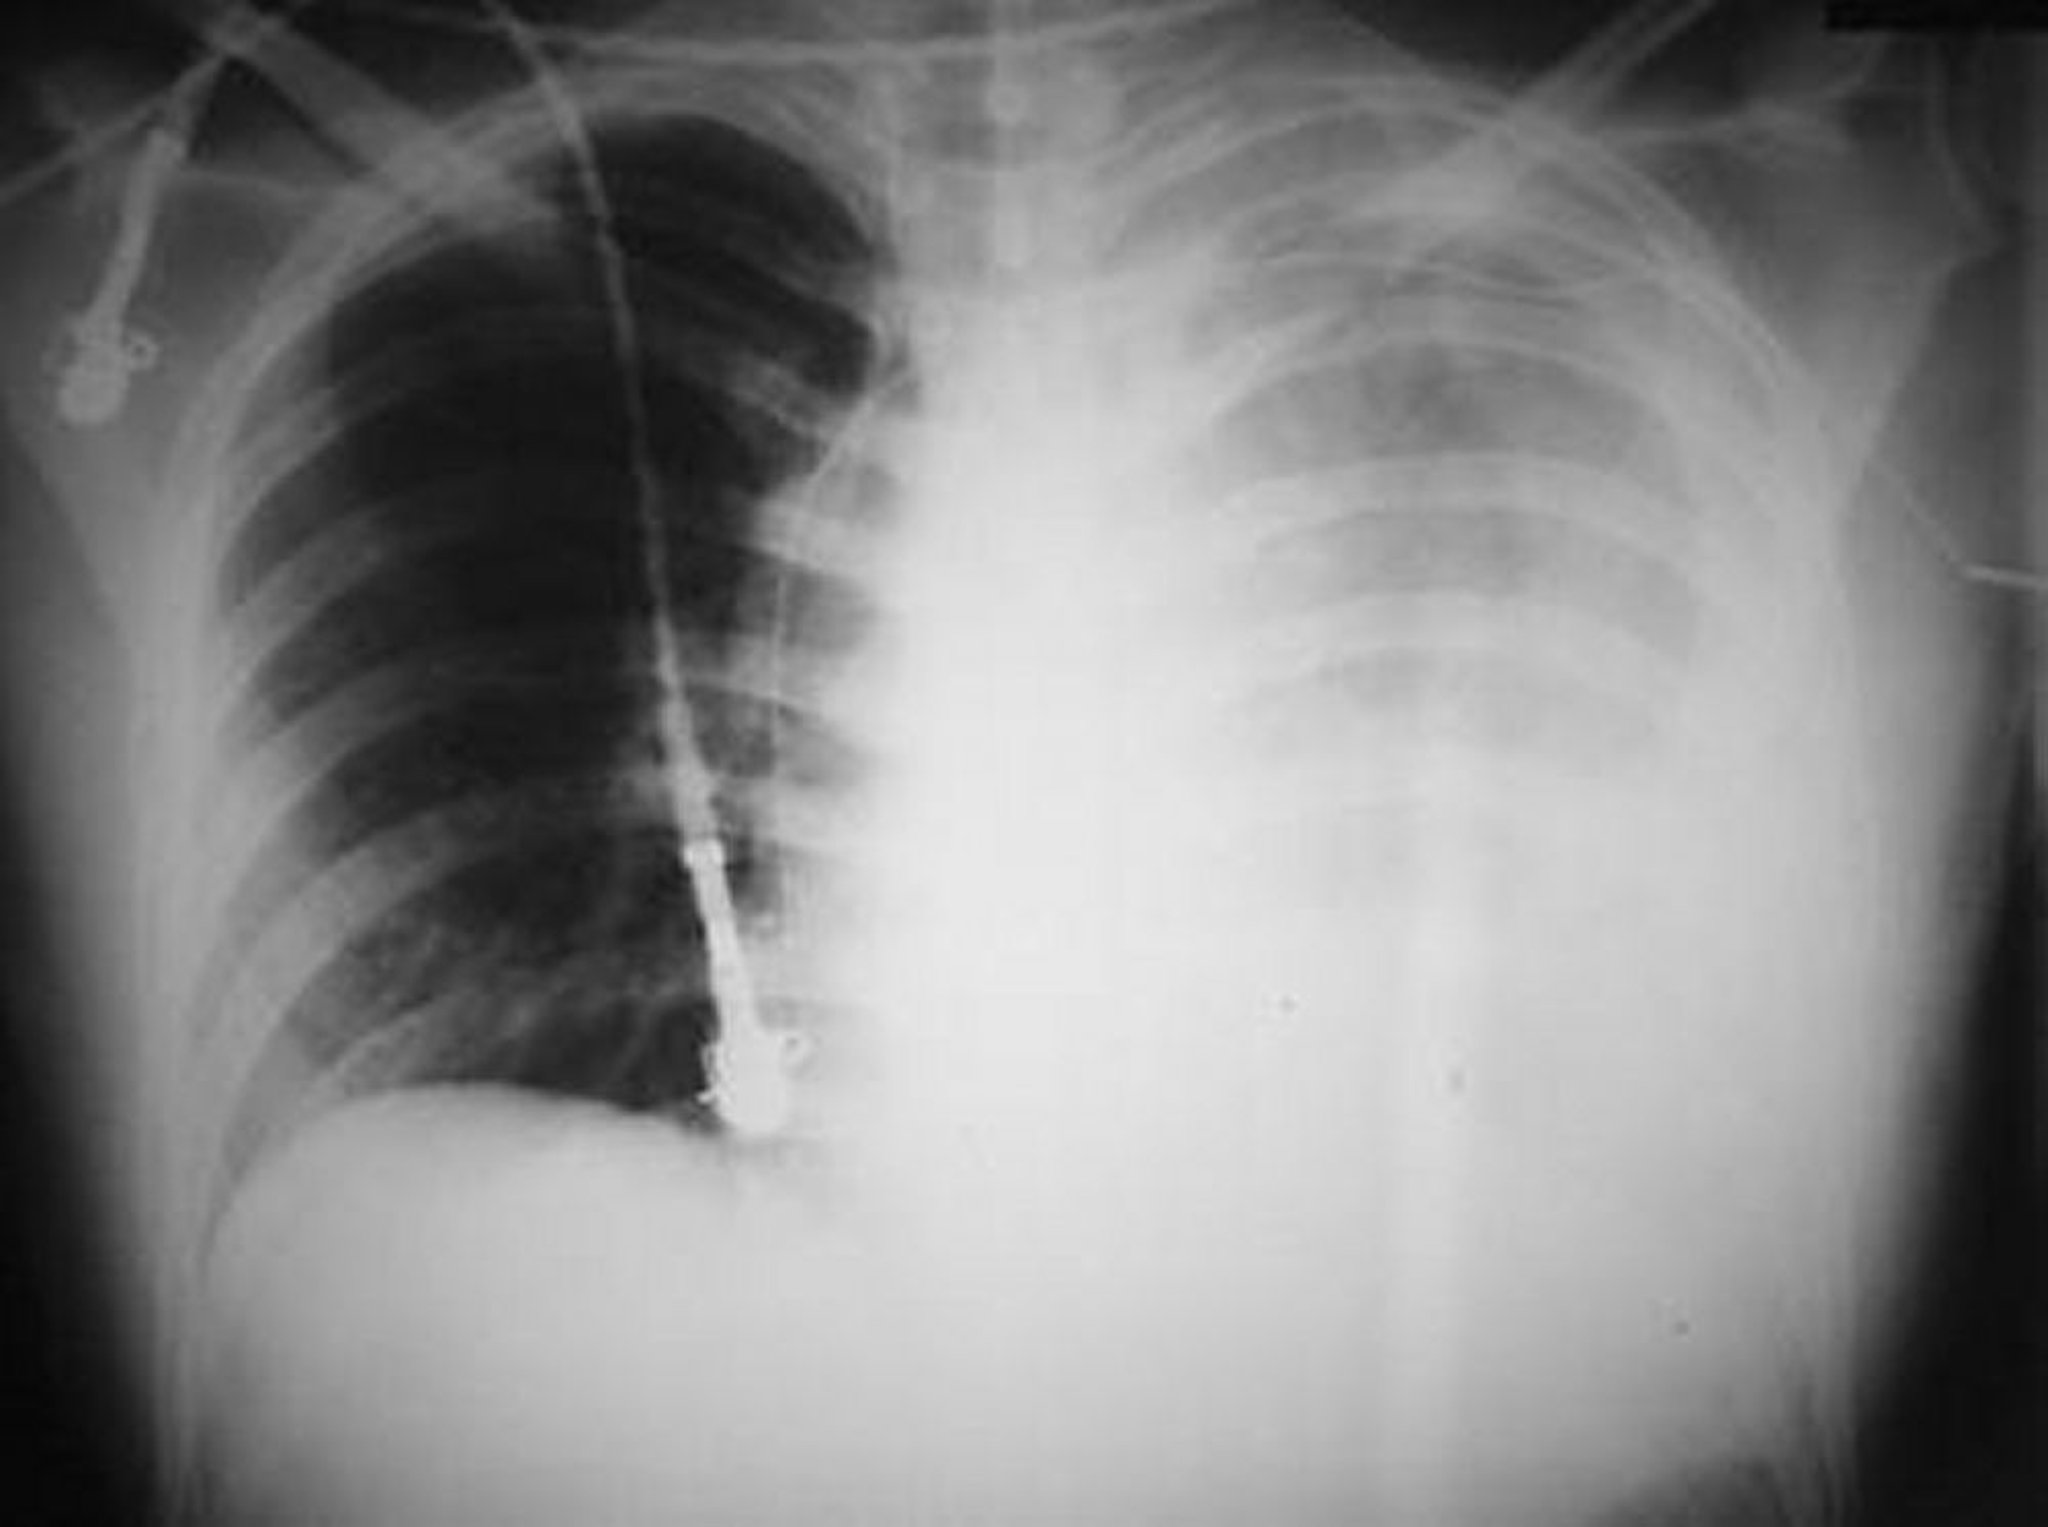

Tràn máu màng phổi

Bức ảnh này cho thấy tràn máu màng phổi nhiều ở bên trái sau khi bị một vết đạn bắn vào ngực trái.